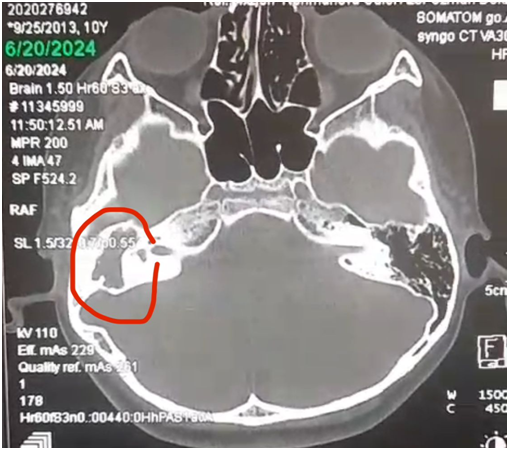

Cədvəldən göründüyü kimi, xolesteotoma ilə bağlı əməliyyat olunan xəstələrin daha çox sayı IV və V yaş qruplarındadır (20% və 44%). Xoleosteotomiya olan xəstələrdə üz kanalının köndələn kəsik sahəsinin ölçüləri artaraq, orta hesabla 2,45±0,18 mm2 təşkil edir (şək.1,2,3). Təsirə məruz qalmayan tərəfdə isə kanalın köndələn kəsik sahəsinin göstəriciləri 1,83±0,23 mm2 təşkil etmişdir ki, bu da bizim normativ dəyərlərimizlə üst-üstə düşür. Bu göstəriciləri hər iki tərəfdən müqayisə etdikdə, təsirə məruz qalan tərəfin köndələn kəsik sahəsinin ölçülərində 1,34 dəfə artım qeydə alınıb ki, bu da 74,7% təşkil etmişdir.

Bu məlumatlar digər müəlliflərin [4,5,6] belə birfikrini təsdiqləyir ki,üz kanalının təbil seqmentinin köndələn kəsik sahəsinin göstəricilərinin artması təbil damın çox nazik olmasının nəticəsidir ki, buna görə də xolesteatoma kimi həcmli proseslər asanlıqla üz kanalının divergensiyasına səbəb ola bilər. Tədqiqat işində xolesteatoma olan xəstələrdə üz kanalının ikinci dizinin bucağı ilə kanalın divergensiyası arasındakı əlaqəyə diqqət yetirilmişdir.